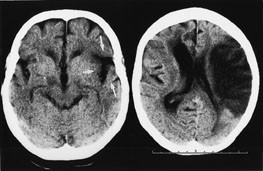

De følgende eksempler er hentet fra pasienter innlagt i Nevrologisk avdeling, Haukeland Sykehus, med akutt cerebral iskemi og undersøkt med CT innen tre timer og ti minutter etter symptomdebut (bildet til venstre, fig 1 – 4) og med oppfølgende CT (bildet til høyre, fig 1 – 4). Bildene illustrerer de forannevnte kardinaltegn (tab 1).

Hypodensitet i basalgangliene (fig 2). Ved et mediainfarkt er basalgangliene (nucleus caudatus, putamen og pallidum) ofte først rammet. Putamen er fysiologisk mer hyperdens enn pallidum.